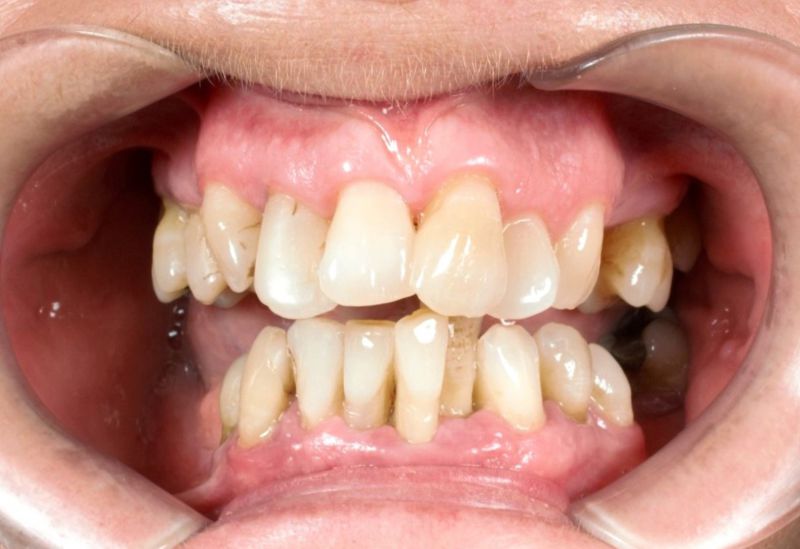

Zobacz przypadek naszej pacjentki

Choroba przyzębia, w wyniku zaniku kości doprowadza często do problemów estetycznych. Poniżej prezentujemy przykład kompleksowego leczenia naszej pacjentki, która zgosiła się z zaawansowaną chorobą przyzębia. Zastosowano zabiegi periodontologiczne mające na celu zatrzymanie progresji zaniku kości, a następnie wykonano odbudowy protetyczne w celu poprawy estetyki uśmiechu i uzupełnienia brakujących zębów.